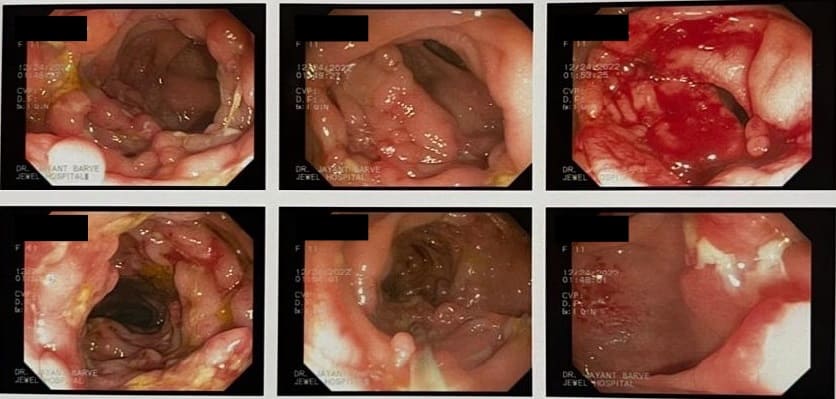

COLONOSCOPY

Colonoscopy is a procedure where the doctor can examine the lowermost part of the digestive tract

by a flexible instrument called as Colonoscope. Common indications for Colonoscopy are

Altered bowel habits, watery or semisolid stools, gripping pain in abdomen, mucus and blood in the stool,

incomplete evacuation can all be due to a condition called as colitis. Colitis has got different causes

like ulcerative colitis, Crohn’s disease, infections, tuberculosis, amoebic colitis, bacillary dysentery and many more.

Corrcet diagnosis by Colonoscopy will allow patients to be treated properly.

IBD - Crohn's Disease

Crohn's Disease